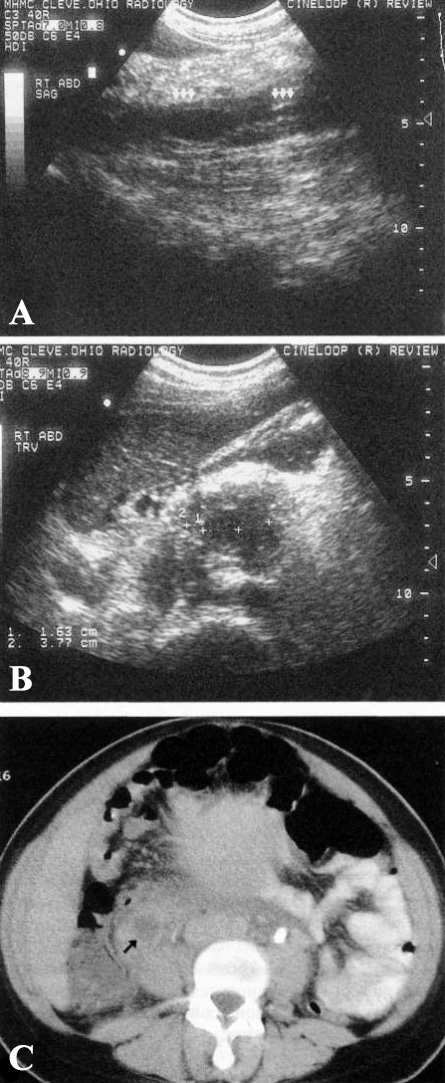

Остатки плодного яйца (остатки плацентарной ткани) на УЗИ представляют собой эхогенное образование в полости матки. Гетерогенное образование или скопление в центральной полости состоит из кровяных сгустков и/или остатков плаценты с некротизированными волокнами (фото 4).

Фото 4. Остатки плодного яйца. А – УЗИ в сагиттальной проекции; В – УЗИ в поперечной проекции. На изображении определяется гиперэхогенное образование в полости матки (между курсорами), характерное для остатков плодного яйца

С помощью цветной допплерографии дифференцируют васкуляризированные ткани с неваскуляризированными, что дает возможность идентифицировать сохранившуюся васкуляризированную плацентарную ткань (неваскуляризированная плацента не имеет кровотока). Остатки плодного яйца маловероятны, если визуализируется нормальное изображение эндометриальной полоски или точечные эхогенные очаги, не связанные с отдельным образованием.